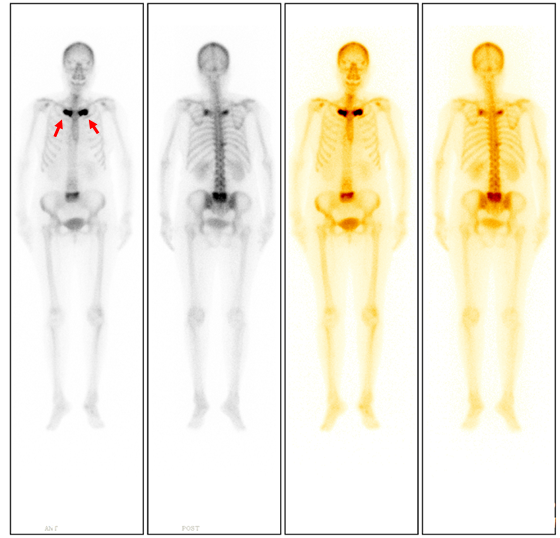

ECT全身骨顯像所見(圖1):

ECT檢查結論:雙側第1前肋、T10、右側第10肋椎關節、腰骶椎(L5為著)代謝異常增強,符合SAPHO綜合征影像學表現。

如果臨床上懷疑SAPHO綜合征,最需要做的檢查是ECT全身骨掃描。ECT可特征性表現為前上胸壁異常放射性濃聚灶,典型的圖像為“牛頭征”(圖1箭)。早期診斷、及時治療能夠避免患者并發癥的發生。同時,ECT能夠展示全身骨骼受累的情況,準確評估疾病范圍及疾病的活動程度。對于治療期間的患者,ECT隨訪可以評估患者對藥物治療的敏感性,并監測疾病進展。(核醫學科)